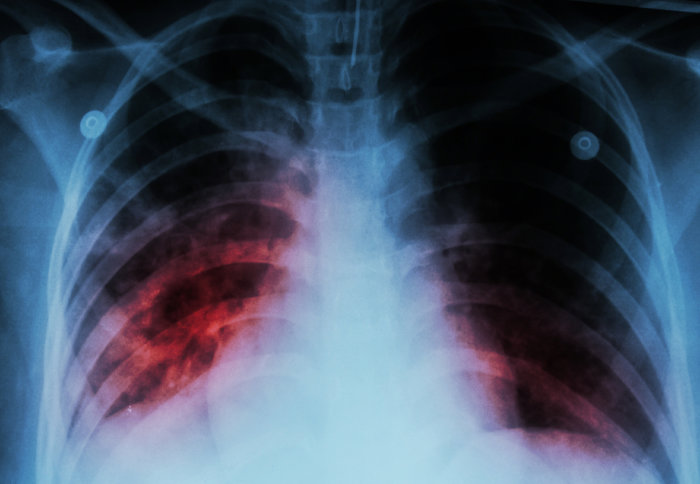

TBC dapat dideteksi melalui pemeriksaan dahak. Beberapa tes lain yang dapat dilakukan untuk mendeteksi penyakit menular ini adalah foto Rontgen dada, tes darah, atau tes kulit (Mantoux). Penyakit ini dapat disembuhkan jika penderitanya patuh minum obat. Untuk mengatasi TBC, penderita perlu minum beberapa jenis obat untuk waktu yang cukup lama (minimal 6 bulan).

Selain pemeriksaan BTA, dokter dapat melakukan serangkaian pemeriksaan lain sebagai pendukung diagnosis, meliputi:

- Foto Rontgen

- CT scan

- Tes kulit Mantoux atau Tuberculin skin test

- Tes Darah IGRA (interferon gamma release assay).